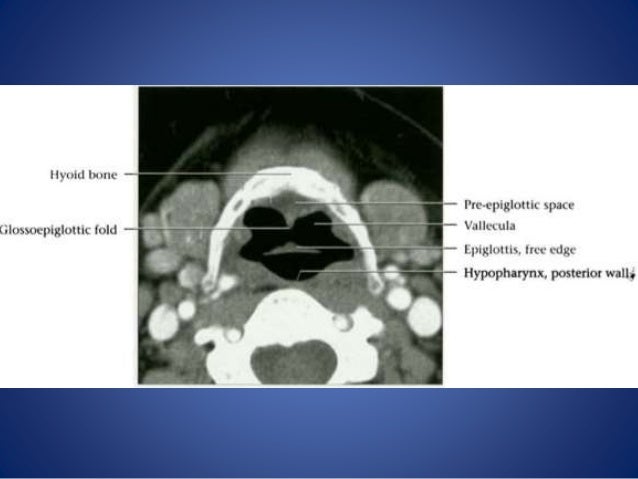

Imaging And Pathology Of Larynx (2)

larynx cartilage arytenoid dislocation vcp mimic vocal